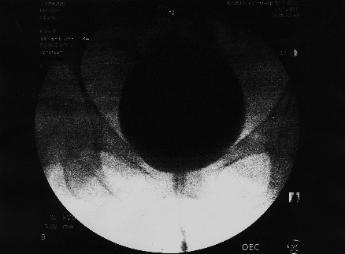

The first five "thermal paper" VUCG images

(mailed to patient by the Kaiser Diagnositic Imaging Department on July 5, 2011)

Kaiser Permanente claimed that these were the only images saved from the VUCG procedure.

How did Dr. Grimaldi manage to write the above report based on these five images?  There is

no urethra visible at all, female or otherwise.

The Diagnositic

Imaging Department

claimed that only this

image and four others

were saved from a

long series of x-rays.

Why would anyone

print this out if he

were only going to

print out a total of five

images?

Dave Horton and

Rhianne Steins are

charge of the

Diagnostic Imaging

Department at Kaiser.

Kaiser claimed that an

official medical report

was produced by

radiologist Jay

Grimaldi five days

later based only on

these five images.

The patient had been

told during her

procedure that all the

images were digitized,

and they would be

available to any doctor

in Kaiser within a few

hours.  In fact, the

digitized images

were "unavailable"

to the patient's

doctor and even to

Emergency Room

doctors.

These images show

the bladder, but

do

not show the

urethra, which was

the

entire purpose

of taking the x-rays.

Is there something

going on with the

urethra that Kaiser

doesn't want to talk

about?

This is

an out-of- focus

"SCOUT" image

.

It gives no useful

information.

There is

no chance that a

doctor who was only going to

print out five images (the

most significant images)--of a

digital video lasting several

minutes--would print out two

scout images.  The truth is

that the whole video was

saved, and these images

were chosen presicely

because they give no